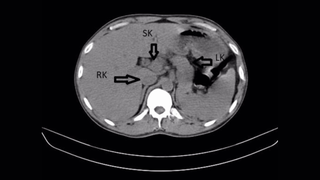

A California woman was scheduled to have a large cyst removed but, in the lead-up to the procedure, learned she had a rare ectopic pregnancy.